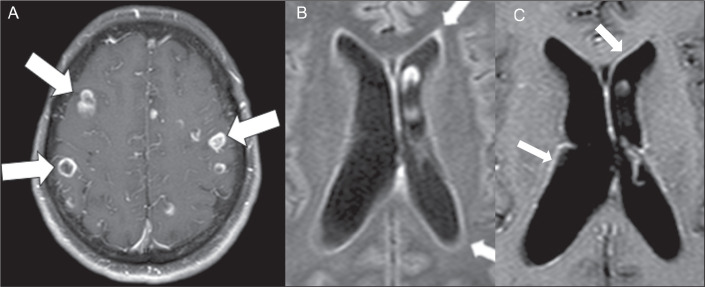

This study involved a retrospective analysis of nine cases of neurocryptococcosis (eight from our institution and one from another institution) seen between May 2014 and May 2022, together with a systematic review of the literature indexed in the PubMed, Embase, and Lilacs databases. Clinical and radiological features of those cases were further refined via an additional comprehensive literature review. The following search string was employed: cryptococcosis AND central nervous system AND (magnetic resonance imaging OR X-ray computed tomography). The search was limited to articles published between July 1978 and May 2022. Two authors, working independently, searched for and selected studies that met the inclusion criteria, and another author reviewed conflicts in a blinded manner. We used Rayyan.ai software to organize the studies, and the review was structured in accordance with the 2020 Preferred Reporting Items for Systematic reviews and Meta-Analyses guidelines. Understanding the prevalence of different patterns of neurocryptococcosis is crucial for improving diagnosis and supporting decision-making in clinical practice. Our review of the literature demonstrated that imaging examinations are a valuable resource for early diagnosis, as well as for assessment of the initial extent and pattern of the disease.